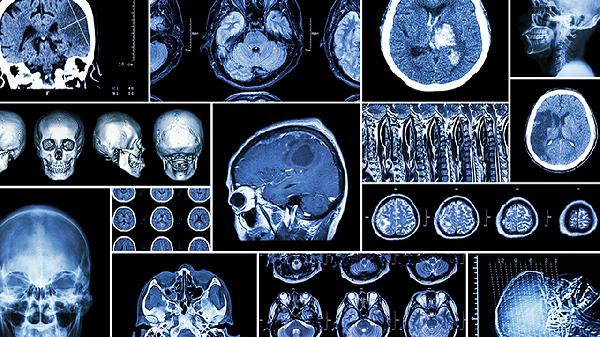

規(guī)范產(chǎn)前檢查可早期發(fā)現(xiàn)發(fā)育異常,妊娠11-14周需進(jìn)行NT超聲篩查。三維超聲能評(píng)估胎兒頭圍生長(zhǎng)曲線(xiàn),發(fā)現(xiàn)發(fā)育遲緩需進(jìn)一步做磁共振檢查。對(duì)于高危孕婦應(yīng)增加產(chǎn)檢頻率,通過(guò)無(wú)創(chuàng)DNA檢測(cè)等技術(shù)監(jiān)測(cè)胎兒狀況。發(fā)現(xiàn)異常需由多學(xué)科團(tuán)隊(duì)評(píng)估處理方案。